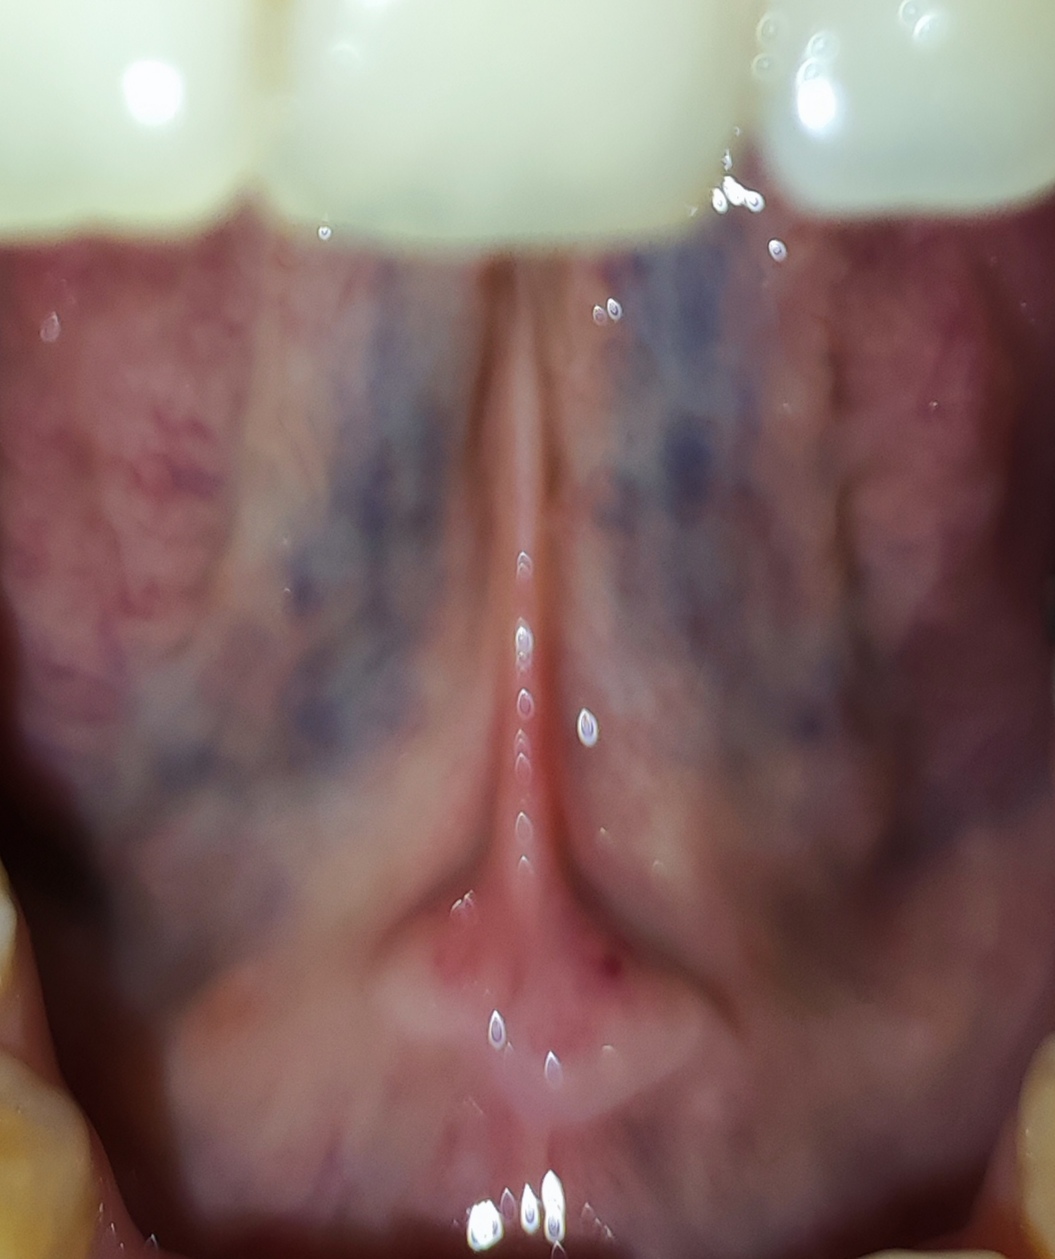

Dobrý deň. Dcéra 27 ročná má takýto jazyk,spodok jazyku je to v poriadku? Fialovo modrý.

Veď to sú normálne žily na jazyku...ty také nemáš?

Však to sú žily 😂

No ze vsetky zily su modre

@anavixy ďakujem čiže je to v poriadku🙂